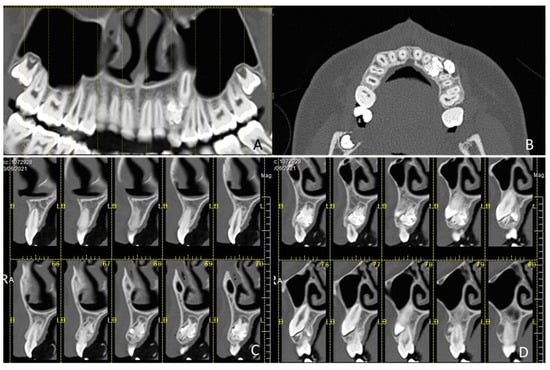

1.1. Case Number 1

1.2. Case Number 2

1.3. Case Number 3